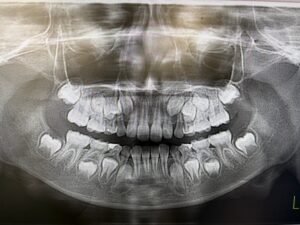

こちらは9歳女子

成長とともに、上手に顎が広がってくれると綺麗な歯並びになりそうです。